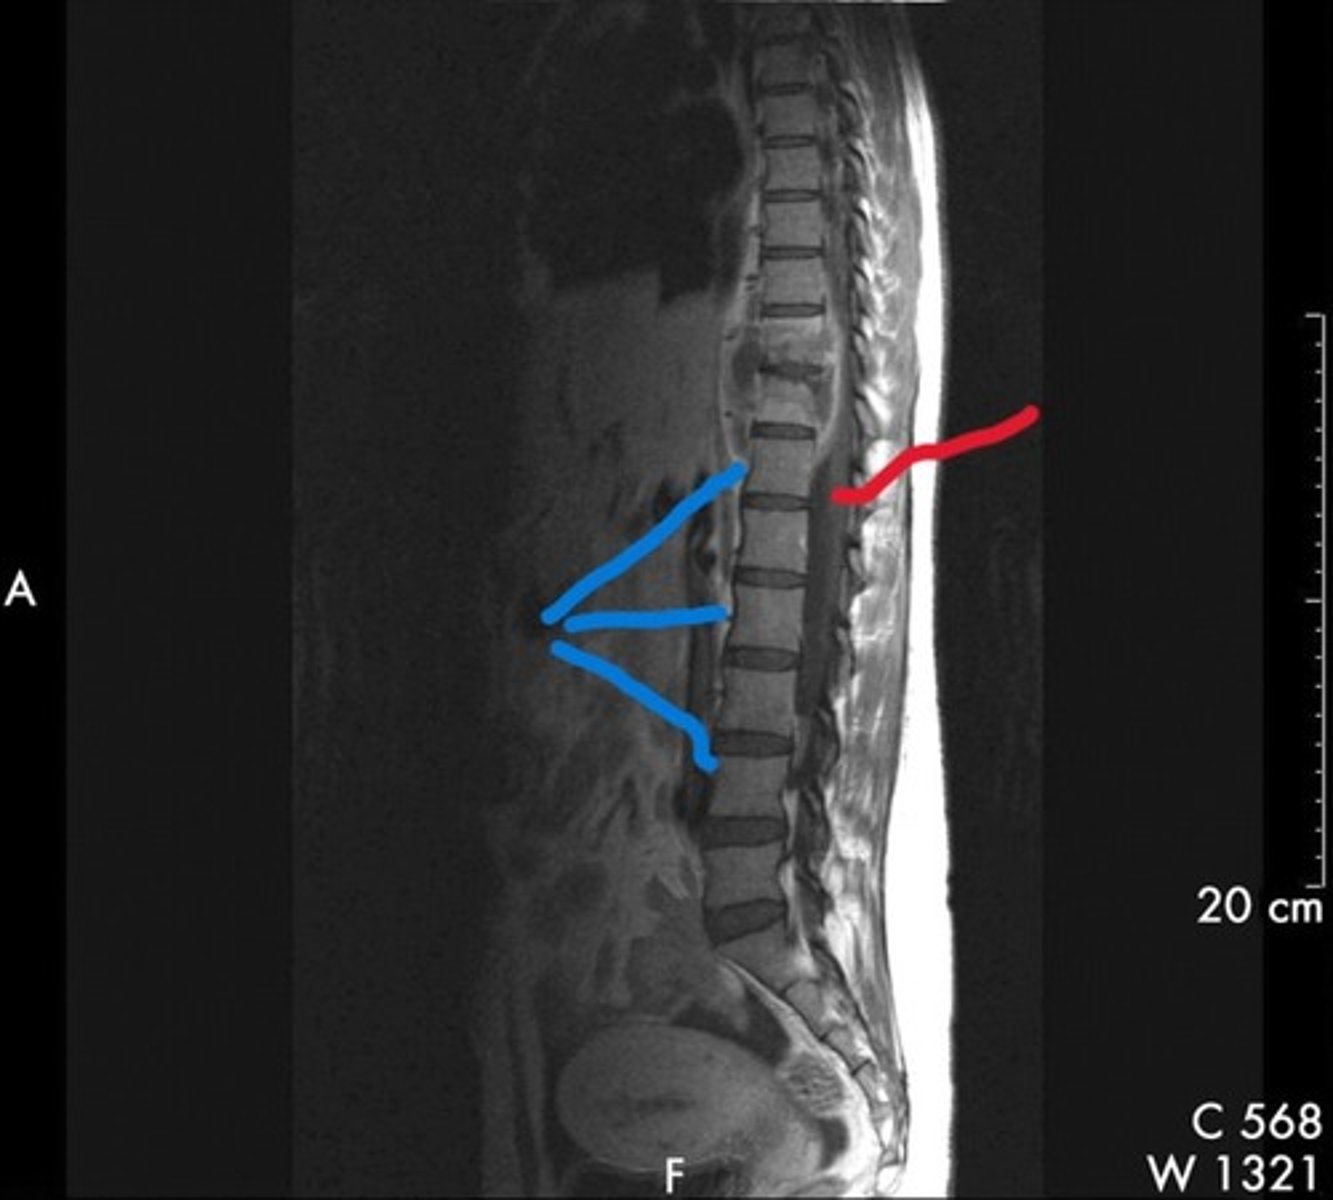

Blue line- vertebral bodies

Red line- spinal canal

What is the blue line pointing to and what is the red line pointing to

Psoas muscles

What are the red lines pointing to

The psoas muscles

What are the blue lines pointing to

Psoas muscles

What are the blue lines pointing to